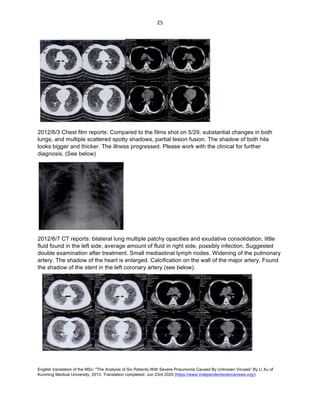

2012/6/3 Chest film reports: Compared to the films shot on 5/29, substantial changes in both

lungs, and multiple scattered spotty shadows, partial lesion fusion. The shadow of both hila

looks bigger and thicker. The illness progressed. Please work with the clinical for further

diagnosis. (See below)

2012/6/7 CT reports: bilateral lung multiple patchy opacities and exudative consolidation, little

fluid found in the left side, average amount of fluid in right side, possibly infection. Suggested

double examination after treatment. Small mediastinal lymph nodes. Widening of the pulmonary

artery. The shadow of the heart is enlarged. Calcification on the wall of the major artery. Found

the shadow of the stent in the left coronary artery (see below).